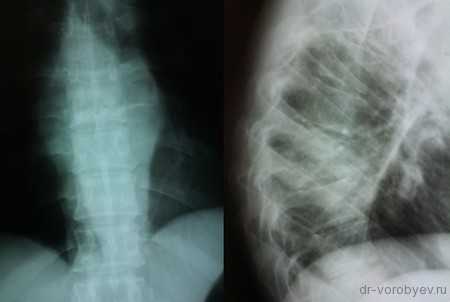

На данных томограммах представлен нестабильный перелом тела Тн12 позвонка

Первым этапом выполнена ламинэктомия с транспедикулярной фиксацией китайской системой, а затем проведена корпорэктомия, корпородез аутокостью и тораколюмбальной пластиной китайского производства.

Пациент с неспецифическим спондилодисцитом в грудном отделе позвоночника

Выполнена операция торакотомия, трансплевральная корпорэктомия, комбинированный корпородез аутокостью и пластиной Centaur фирмы Stryker